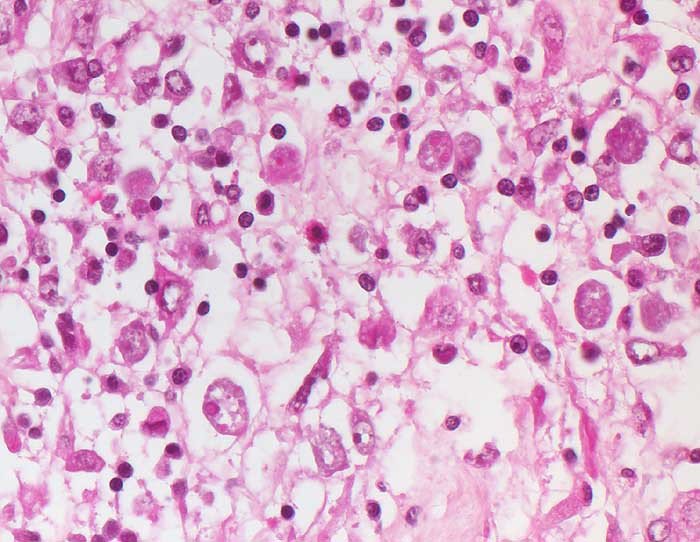

AP/ Amöbenkolitis

Amöbenkolitis

Entzündung infektiös

Darm, Anus

Kolon